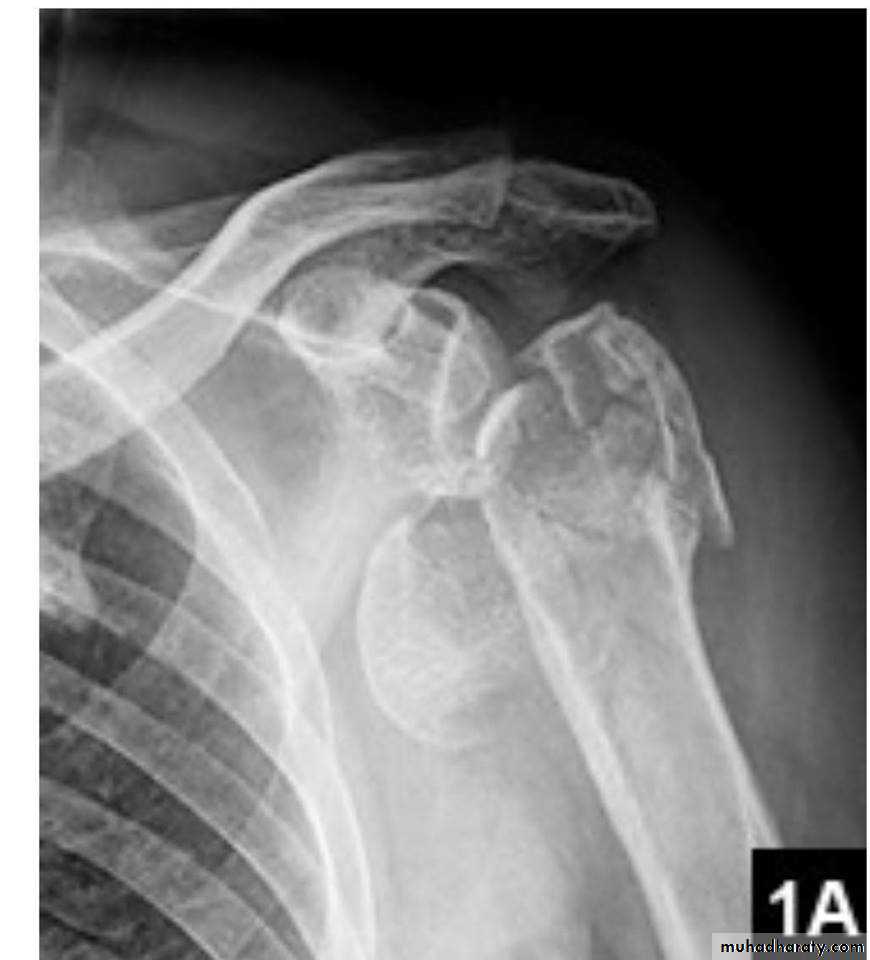

X RAY

27

28